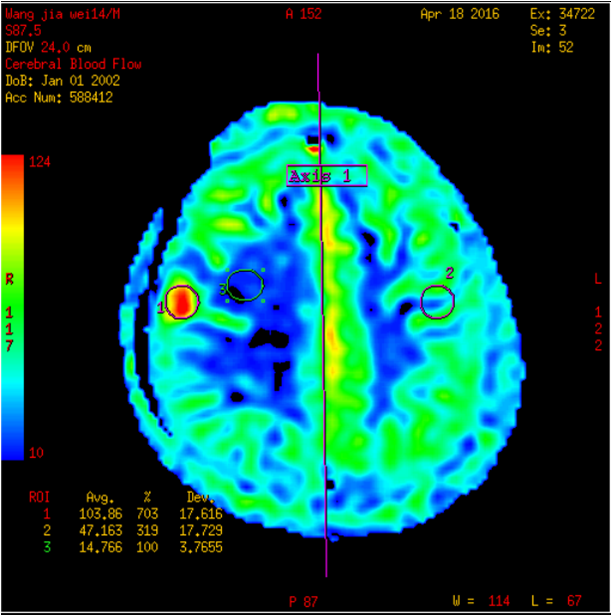

王某某,男,14岁,1年前发热及口角抽搐,在外院抗病毒、抗癫痫治疗,治疗效果不理想,近2周症状加重伴头晕头痛。外院MR:右额不规则异常强化(斑片状、环形强化),考虑感染性病变。既往外院实验室检查:脑脊液免疫球蛋白M0.357mg/L(0.000-0.300);脑脊液葡萄糖:3.54 mmol/L;氯117.2 mmol/L蛋白:0.42g/L;白细胞:8×10^6/L;单核细胞:8×10^6/L;入院完善MR:病灶和外院2015-8-27MR相比,病灶扩大。诊断:右额占位性病变(寄生虫?)

治疗:患者全麻下行右额占位性切除术,术程顺利,术中右额中央前回前方多囊性占位,皮层表面粘连,囊性占位下方与脑组织边界尚清晰,切开囊壁可见中央脓性液体。术中冰冻提示肉芽肿,病理:符合慢性脑脓肿并肉芽肿形成。PAS及GMS染色查见个别真菌孢子,形态较符合着色芽孢菌。诊断:颅内炎性肉芽肿。